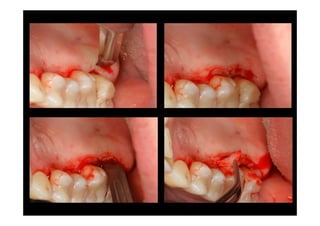

Procedure

The initial gingival incision

"internal reverse bevel incision"

should be made with a knife

that can be directed parallel

to the long axis of the tooth.

A second incision is made

around the neck of each

tooth from the bottom of

the pocket to the alveolar

crest.

Vertical gingival releasing incision usually is not

needed. A full thickness flap is elevated for only 1-2

mm from the alveolar crest as needed for access to

the root surfaces and the interproximal one.

The third and final incision is made with a

narrow interproximal knife. The buccal and/or

lingual flaps are deflected by a periosteal

elevator on top of the alveolar crest to dissect

free the collar of

gingival tissues, which is

been separated from the

buccal and lingual gingival

flaps and the teeth.

The separated collar of

gingival tissue is then

removed with curettes.